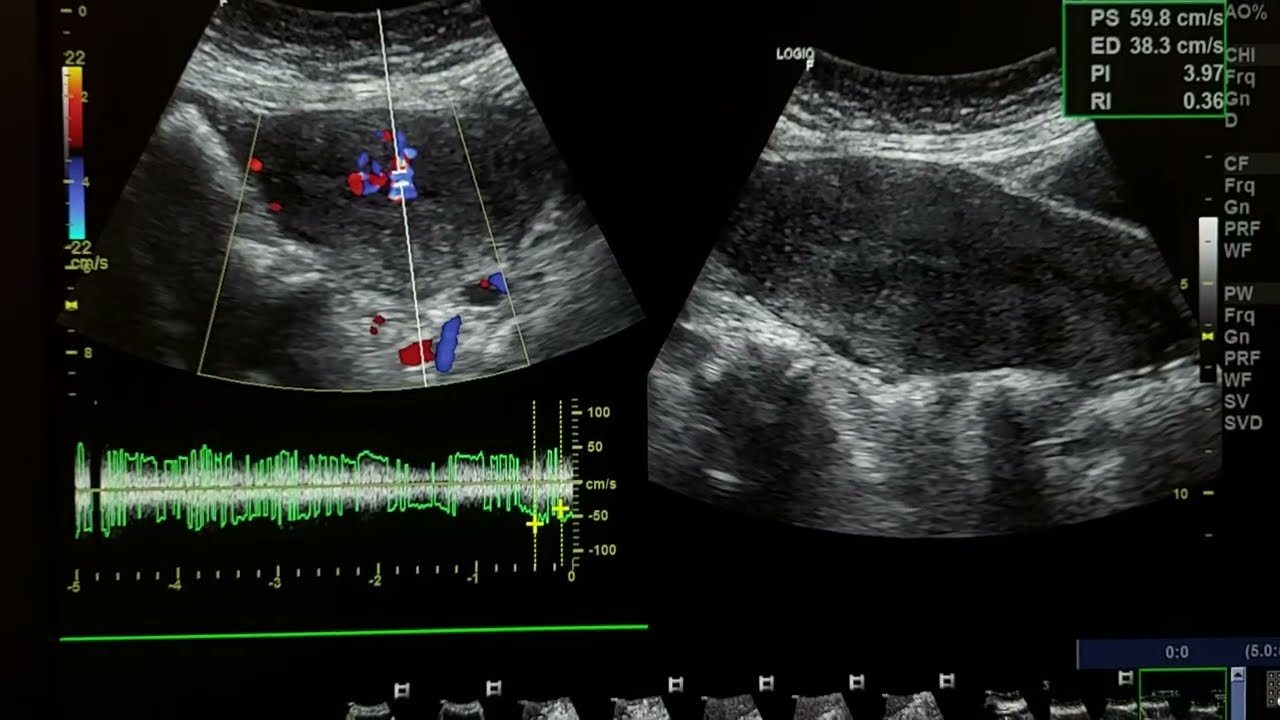

RPOCs in a 40 years old woman with pervaginal bleeding

RPOCs dopplerretained products of conception ultrasoundretained products of conception diagnosisretained products of conceptionhow retained products of conception appear on dopplerpervaginal bleeding causesdilation and curettage miscarriage

retained products of conception

• Retained products of conception